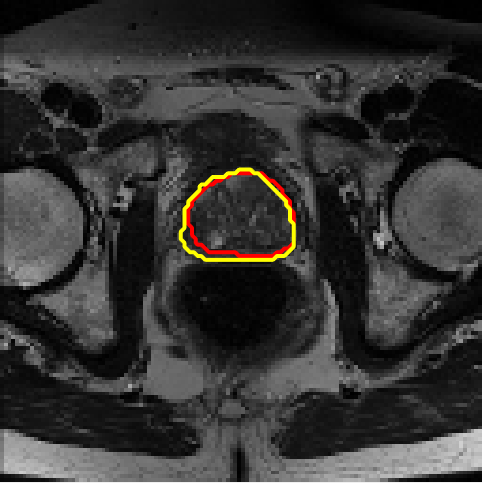

4.4 Results on PROMISE12

We assess different semi-supervised methods on the PROMISE12 dataset (Litjens et al., 2014). The PROMISE12 dataset contains 50 transverse T2-weighted MR images with the most anatomical detail. 35 and 15 cases are randomly selected for training and validation. The images were resized to 128×128128\times 128. The training dataset includes nn fully annotated images, with pixel-wise labels unavailable for the remaining 35n35-n. Table 3 presents the results. Fig. 7 offers a visual comparison of the segmentation results for different models and shows that the proposed method achieves more precise segmentation.

Figure 7: Example segmentation obtained by different methods on the PROMISE12 dataset. Red lines indicate predicted results, and yellow lines indicate ground truths.